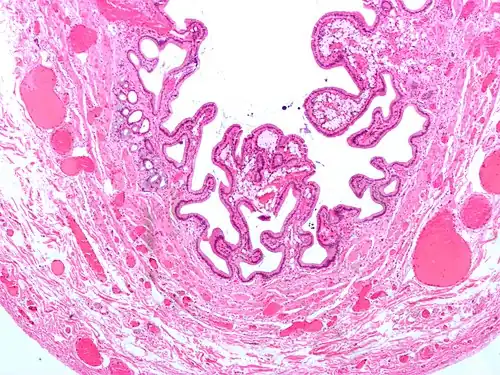

Micrograph of cholesterolosis of the gallbladder